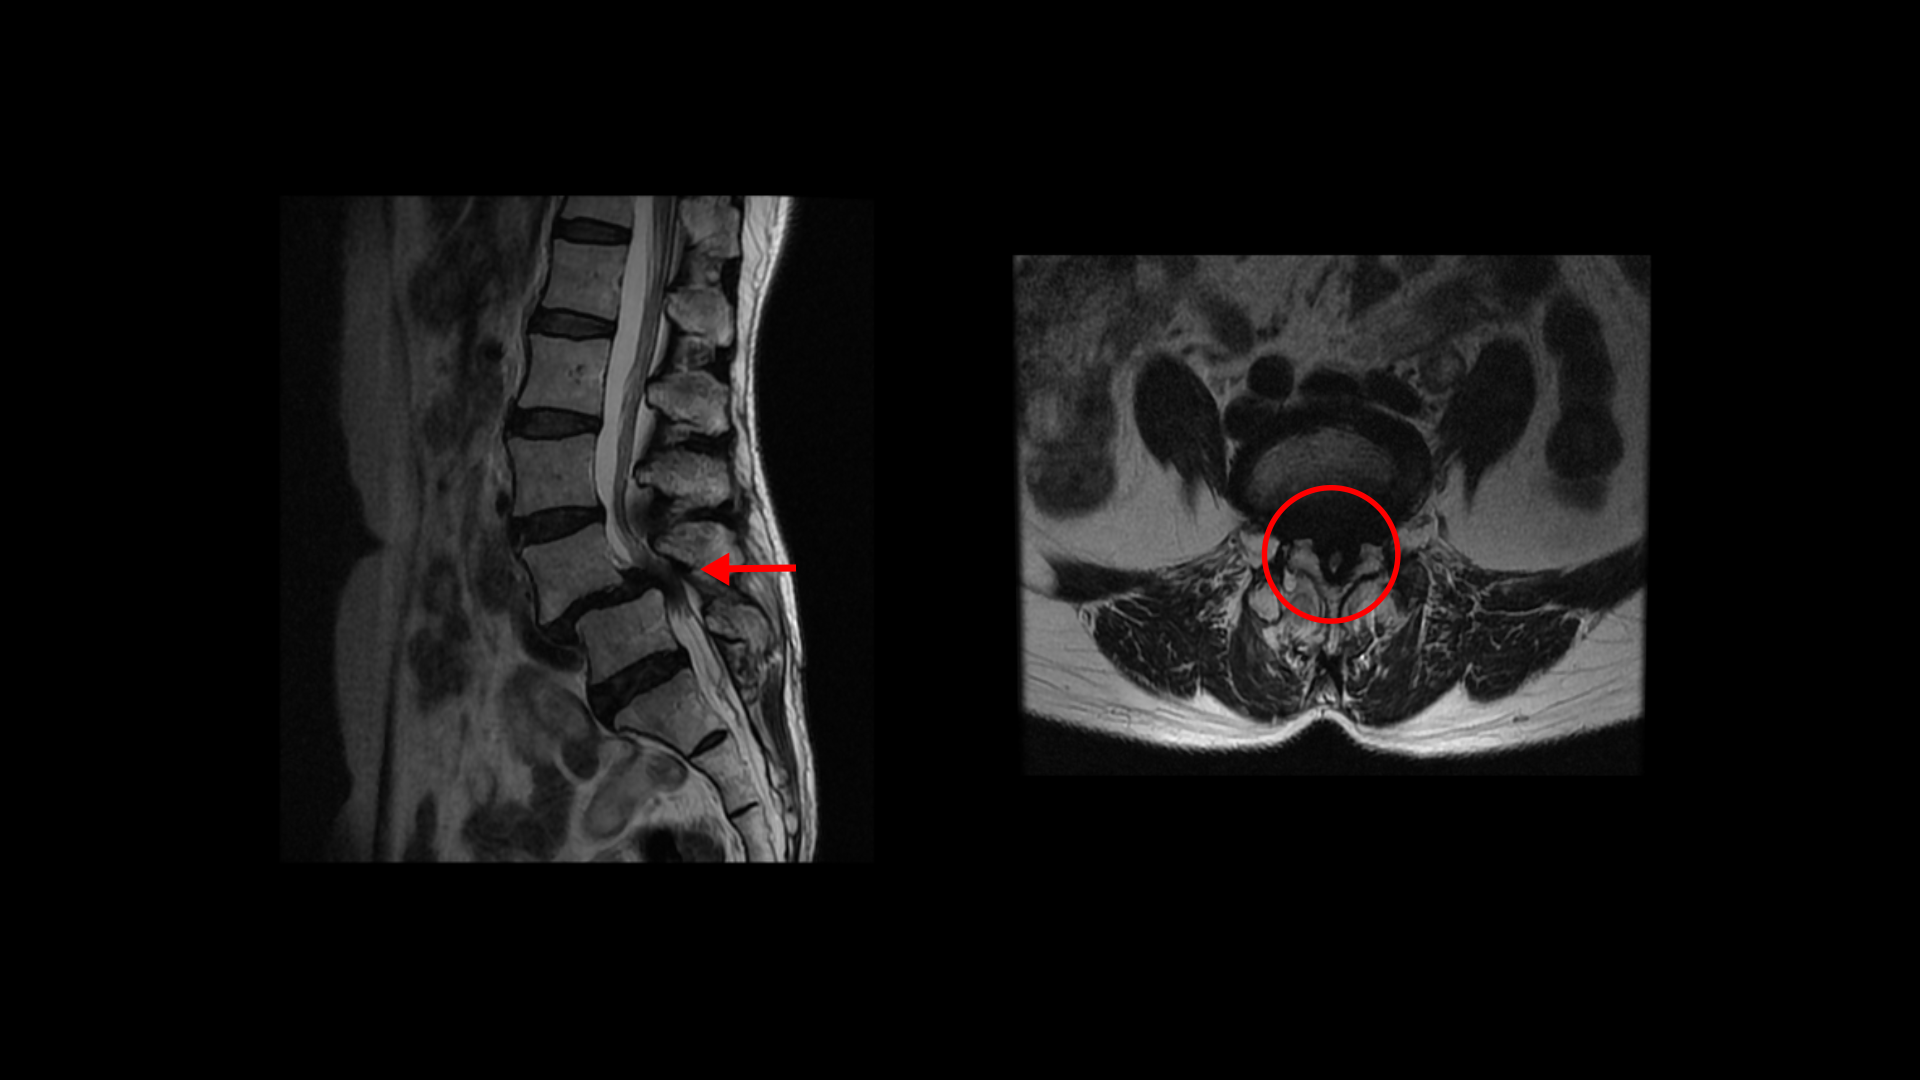

이 환자분 상태를 먼저 설명 드린 후 이분 말씀을 들어보겠습니다. 이분 MRI를 보면 전방전위증과 척추관협착증이 정말 심합니다.

위 뼈가 거의 절반 가까이 밀려 나가있고 두 마디의 척추관이 정말 심하게 막혀서 보시다시피 신경이 제대로 보이지 않습니다.